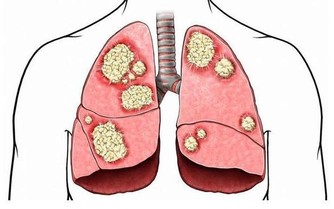

2、菸酒

酒精對胃黏膜有較大的損害,人們在吸煙時候,煙霧中的有害物質,溶解並附著在口腔、咽喉部,隨吞嚥進入胃內,這些有害物質對胃黏膜也有很大損害。因此,急、慢性胃炎患者,一定要戒除菸酒,以免加重病情,甚至造成惡性變。吸煙喝酒與肺癌,胃癌的發生密切相關。